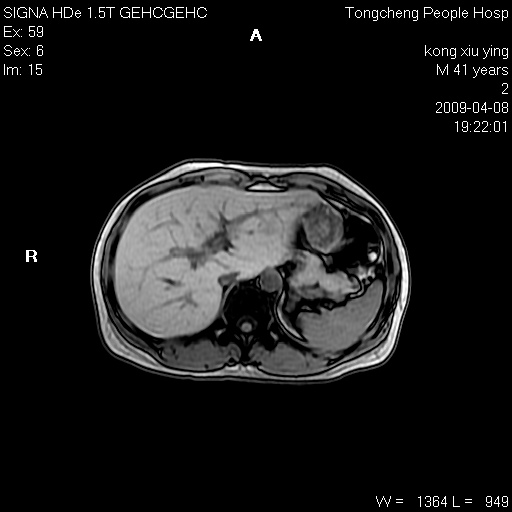

标题: CL1008:【经典】胆囊石榴籽样结石。

女,41岁。健康体检——彩超提示:胆囊显示不清。平素健康,无不适感。

腹部mr扫描及mrcp,图像如下:

标题: 胆囊阴性结石ct图片

好啊!我有ct的插进来啊,楼主请允许噶。